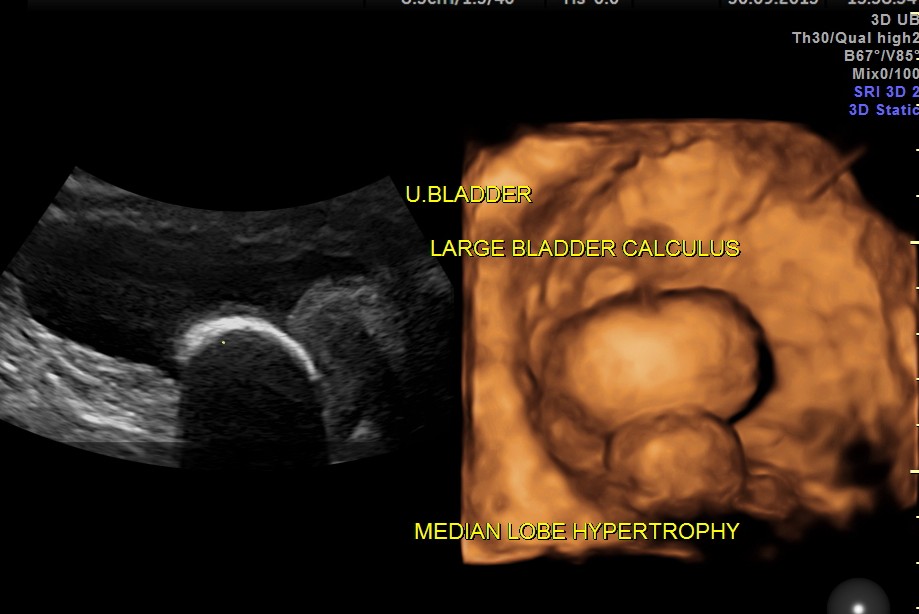

urinary bladder showed a large calculus and prominent swelling of the median lobe of the prostate.

the following images show the 2 d and 3 d appearance of the same.

The diagnosis given was Large calculus in the urinary bladder , Severe prostatic enlargement with prominent median lobe hypertrophy , causing Right sided obstructive uropathy.

The diagnosis was made with the 2D images , but the 3 D images were very helpful in explaining to the patient.